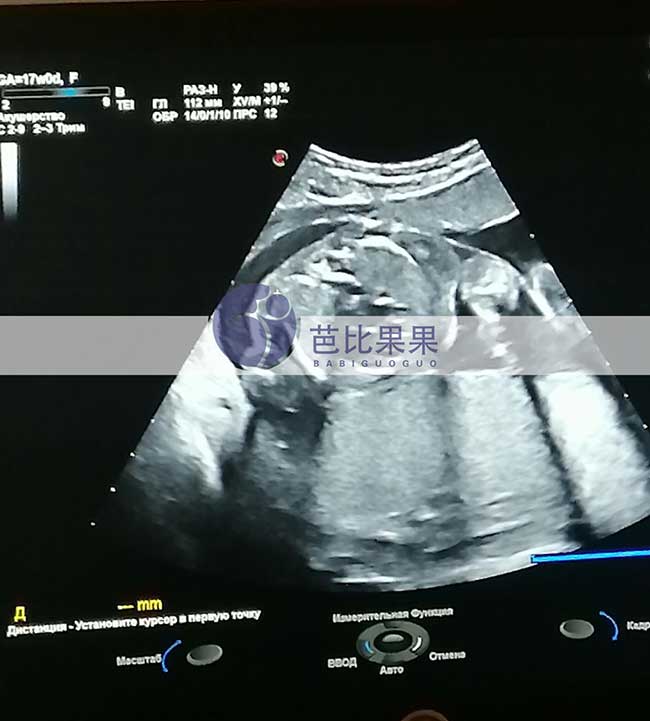

J先生的乌克兰试管妈妈按时基辅妇产医院做孕17周B超孕检

J先生家乌克兰试管妈妈按时到我们熟悉的基辅妇产医院做孕17周B超孕检,胎儿发育得很好,孕妈身体状态也很好,辛苦她了